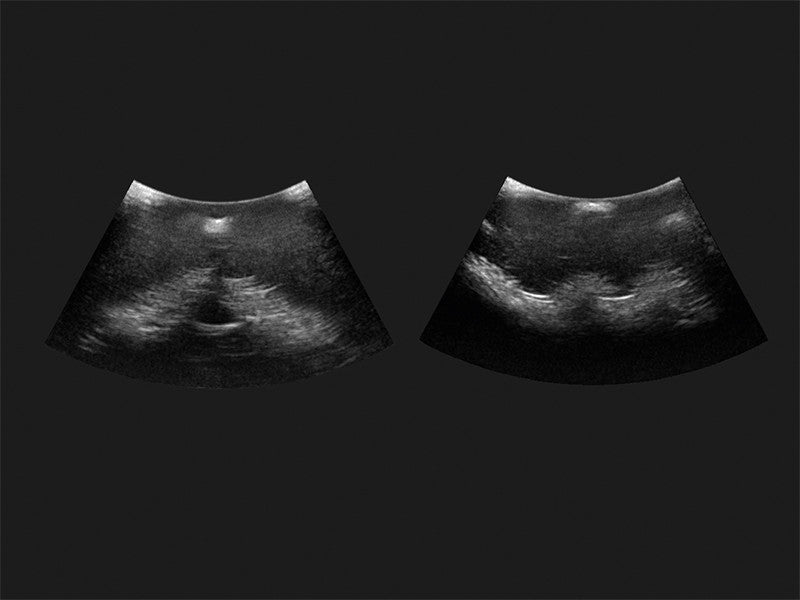

Our range of epidural injection trainers includes detailed anatomical models that replicate the lumbar and thoracic spine, providing a hands-on learning experience for anaesthetists, medical students, and pain management specialists. These advanced simulators allow users to practise needle placement, identify key anatomical landmarks, and develop proficiency in administering epidural and spinal anaesthesia with confidence. Ideal for medical schools, hospitals, and professional training programmes, these epidural trainers support skill development in regional anaesthesia, labour pain management, and spinal procedures. With lifelike materials that simulate real patient responses, our models offer a realistic and immersive training experience.